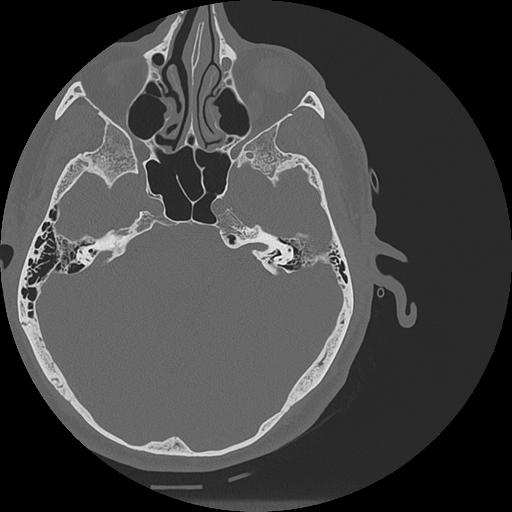

7 HUESO,,Vol,0.5,HUESO,,